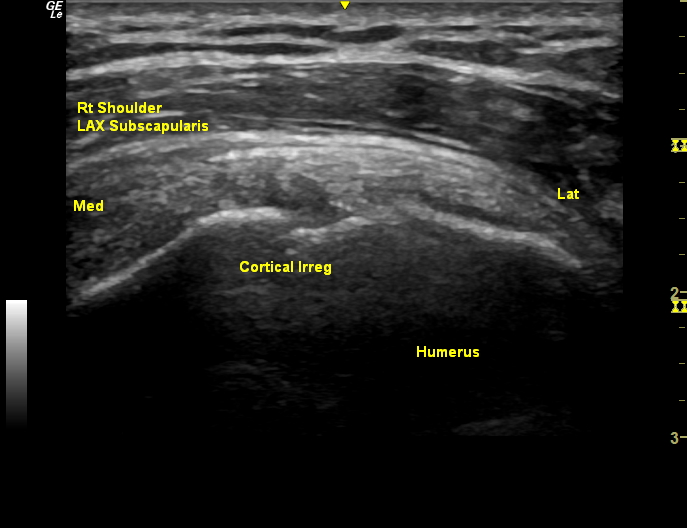

Musculoskeletal ultrasound protocol the shoulder @mskult rasound www. Us7 protocol performed of the pip2, pip3, mcp2,. Msk worksheets the msk worksheets have lists from which you can select and a field for entering comments. To display an msk worksheet A solid understanding of musculoskeletal ultrasound will help physical therapists succeed in this emerging field.

This digital ultrasound worksheet will improve workflow and will increase the consistency of termininology used to report findings of renal artery duplex ultrasound. Msk us exam protocol standardization kenneth lee/dana walker/christina hendricks revised 1/11/2018 standardized diagnostic us exams: The asa has commissioned the university of south australia centre for allied health evidence (icahe) to undertake a research project: Us7 protocol.